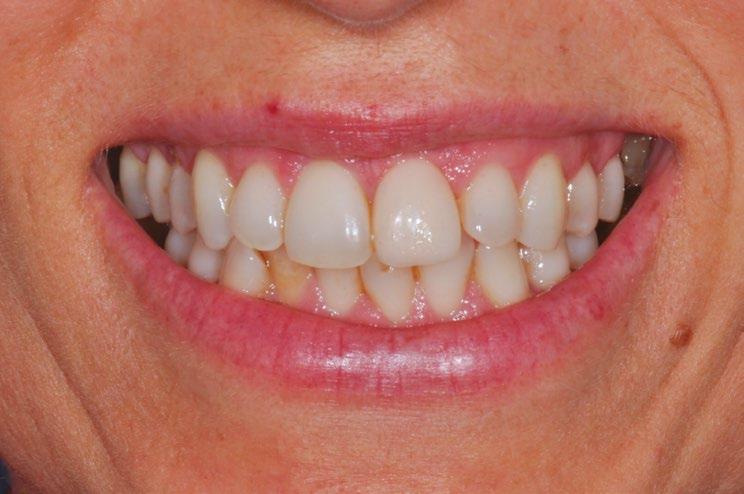

Este abordaje permite conseguir una estabilidad del implante y de los tejidos duros y blandos, y un resultado estético óptimo (Fig. 25, 26, 27, 28). 

14 23 24 25 26 27 28